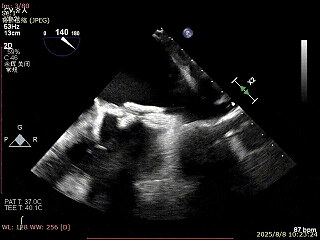

穿刺可用高度不足,通过”A”旋钮旋转180度借高度,此时LVOT切面夹子严重Huge

使用”+”旋钮一键消除Huge

XTR弹道测试

3D enface 完成Orientation调整

成功捕捞瓣叶并夹持